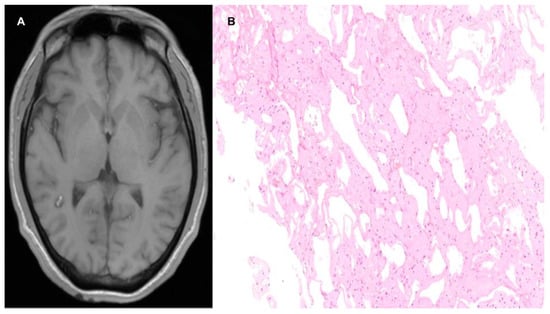

3.3.1. Cerebral Capillary Telangiectasia

- McKinney, A.M. Slow-Flow, Asymptomatic Vascular Malformations: Brain Capillary Telangiectasias and Developmental Venous Anomalies. In Atlas of Normal Imaging Variations of the Brain, Skull, and Craniocervical Vasculature; Springer International Publishing: Cham, Switzerland, 2017; pp. 487–521. ISBN 978-3-319-39789-4. [Google Scholar]

- Larson, A.S.; Flemming, K.D.; Lanzino, G.; Brinjikji, W. Brain Capillary Telangiectasias: From Normal Variants to Disease. Acta Neurochir. 2020, 162, 1101–1113. [Google Scholar] [CrossRef] [PubMed]

- Braileanu, M.; Wicks, J.M.; Saindane, A.M. Appearance of an Unusual Ring Enhancing Brain Capillary Telangiectasia on 3.0T MRI with Dynamic Susceptibility Contrast Perfusion. Radiol. Case Rep. 2020, 15, 1331–1334. [Google Scholar] [CrossRef]

- Liu, Y.; Liang, Y.; Tong, F.; Huang, W.; Tinzing, L.; Le Grange, J.M.; Wang, F.; Zhou, Y. Sudden Death from an Epileptic Seizure Due to Capillary Telangiectasias in the Hippocampus. Forensic. Sci. Med. Pathol. 2019, 15, 243–248. [Google Scholar] [CrossRef]

- Tao, Y.; Sun, X.; You, Y.; Chen, J.; Wang, J.; Wang, S.; Lin, N.; Liang, B.; Zhao, J. Symptomatic large or giant capillary telangiectasias: Management and outcome in 5 cases. J. Neurosurg. 2016, 125, 160–166. [Google Scholar]